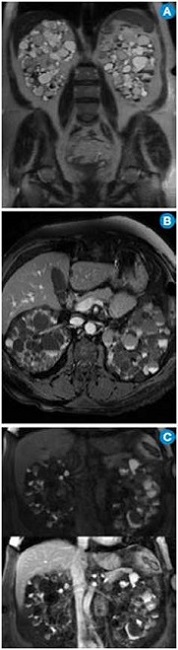

Por su alta sensibilidad, disponibilidad y bajo costo, la ecografía renal es el estudio inicial con el que se pueden observar riñones grandes con quistes bilaterales, múltiples y tamaño variable (figura 1); sin embargo, es altamente dependiente del operador y es menos sensible para detectar quistes <1cm que se visualizan mejor en la escanografía o en la resonancia magnética 24. Pese a que en la actualidad no existen criterios estandarizados en estas dos técnicas imagenológicas para el diagnóstico de la PKD, la tomografía computarizada (TC) y la resonancia magnética (RM) son más sensibles para el diagnóstico de los quistes en los casos dudosos, la detección de complicaciones, la valoración de la progresión y la respuesta al tratamiento 25 (figura 2).

En la ARPKD, el diagnóstico puede ser realizado en el período intrauterino, neonatal o en los primeros meses de vida por medio de una ecografía renal en la que se observan los riñones aumentados de tamaño, con pérdida de la relación corticomedular, hipoplasia pulmonar y oligohidramnios debido al bajo gasto urinario 31. En edades posteriores se prefieren las imágenes por TC y RM para seguimiento o, como ya se mencionó, para casos dudosos. En las fases tempranas, los riñones pueden ser de tamaño y forma normal; en las fases posteriores aumenta el número y el tamaño de los quistes, con distribución difusa del parénquima, aumento del tamaño (se alcanzan longitudes de hasta 40cm) y, por consiguiente, aumento del volumen renal. La RM es la técnica de elección empleada para la volumetría de los quistes y del parénquima como indicadores de progresión o de respuesta al tratamiento.